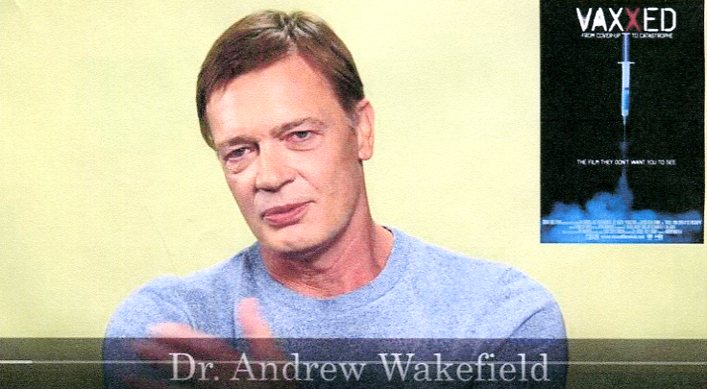

listen HAPPY CHRISTMAS JOHN LENNON Elon Musk: "I'm dark MAGA" IT'S HOWDY COVID TIME PHARMA-GOV'T EVIL DRUG SAFE-SUPPLY MMR = MONEY-MAKING-RACKET = AUTISM Life of John A Macdonald is History of Canada DAVE HOOK RANTS I'M CANADIAN HAPPY BIRTHDAY 121 GEORGE ORWELL ORWELL-COLLEY-JURA & MR JONES ORWELL'S EILEEN'S JULIA IN 1984 CANNABIS TRUTH-HOPE-CHANGE DEVOTEE DIES 13.BIG HORN CAVALRY DIDN'T COME MEMORABLE JFK SOLOMON SWIMS Europe's Angry Farmers Stirring Revolt Coal for Canucks bad; good for Commie Chinks Carbon "axe-the-tax" protests across Canada BRAIN-EATING COVID ZOMBIE VAX

watch HEAR THE SILENCE Autism Movie, YouTube